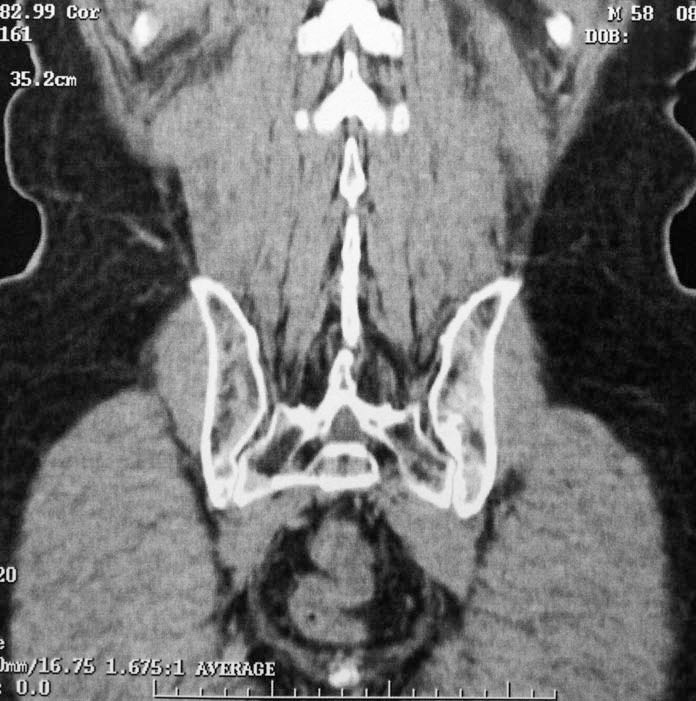

Es gab 14 neue, klinisch bedeutsame Diagnosen: Zehn wurden durch beide Methoden entdeckt, vier nur durch die konventionelle Autopsie, nämlich zwei Lungenembolien, eine alveoläre Proteinose und eine septische Kniegelenksarthritis (außerhalb des CT-Areals). Von 88 weiteren Nebendiagnosen wurden 26 durch beide Methoden, 27 nur durch virtuelle und 35 nur durch konventionelle Autopsie entdeckt. Bei der Computertomografie werden vor allem Karzinome, Thrombosen, Lungenembolien und Myokardinfarkte, bei der konventionellen Autopsie vor allem Frakturen, Pleura- und Perikardergüsse, Pneumothoraces und Fremdkörper übersehen.

Ein CT deckt Diagnosen auf, die selbst der Autopsie entgehen.